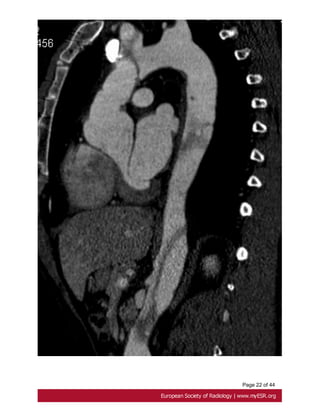

Fig. 12: Stanford type A dissection. Reformated CT scan shows an annuloaortic ectasia

and an aortic dissection with involvement of brachiocephalic artery.

Page 9 of44 or leak at proximal and distal graft anastomoses and at coronary reimplantation site [17]. Fig. 8 on page 17, Fig. 9 on page 18, Fig. 10 on page 19 • Aortic dissection Aortic dissection is characterized by separation of the layers of the aortic media initiated by a primary intimal tear[10]. Stanford type A dissection, which involves the ascending aorta, should be treated as a surgical emergency. Uncomplicated Stanford type B dissection, which is confined to the aortic arch and the descending aorta, can be treated with medical therapy[18]. Fig. 11 on page 20 ECG-gated CT is the first line investigation in acute dissection. Procedure include a non contrast study to look for intramural hematoma, and a contrast study. CT shows the false lumen which is separated from the true lumen by an 'intimal flap", and the extension of the dissection and any involvement of aortic branch vessels. Fig. 12 on page 21 MRI is recommended for long-term for follow up patients with Stanford B dissection, to appreciate changes in the size of the dissected aorta .Its use in the acute dissection is limited by a prolonged study duration [19]. Fig. 13 on page 23 • Bicuspid aortic valve Prevalence of bicuspid aortic valve in Marfan patients is about 5% whereas it is 1-2% in the general population. A bicuspid valve has two cusps instead of three; most commonly they are unequal size because of congenital fusion of one of the valves commissures [20]. Bicuspid aortic valve is generally detected by transthoracic echocardiography. ECG gated and contrast-enhanced CT shows two completely developed cusps and commissures [21]. Fig. 14 on page 23 • Mitral valve About 65 % of patients with Marfan's syndrome have mitral valve prolapse. Compared with myxomatous disease patients, Marfan patients have longer and thinner mitral valve leaflets, less posterior leaflet prolapsed and more anterior or bileaflet prolapse[22]. • Pulmonary artery

Page 23 of44 Fig. 12: Stanford type A dissection. Reformated CT scan shows an annuloaortic ectasia and an aortic dissection with involvement of brachiocephalic artery. Fig. 13: Stanford B triple-barreled aortic dissection. Axial black blood spin echo imaging shows a dissection of the descending aorta.